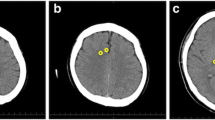

MRI acquisition was routinely performed with 3 T Siemens MR Scanners (Magnetom Vida, Magnetom Verio or Magnetom Skyra fit; Erlangen/Germany). Certified staff neuro-radiologists from the Department of Neuroradiology of the Inselspital, University Hospital Bern quantified MRI findings as part of their clinical routine. The MRI report based on four different patterns known as MR-lesion patterns (MLP), originally described by Barth et al. [13]. According to this publication, MRI findings were classified based on the DWI and apparent diffusion coefficient ADC restrictions. An axial T2w and a coronal T2w-FLAIR (Fluid-Attenuated Inversion Recovery) were used to detect old hyperintense abnormal signal alterations, to exclude chronic infarction, or as a reference to exclude T2- “shine through” effect. ADC values were measured in pre-defined regions of interest located in the cerebral cortex, the cerebellar cortex, the hippocampi, the basal ganglia, both thalami and the brain stem. The cerebral cortex contained eight regions of interest’s (one in each frontal, parietal, temporal, and occipital lobe). Region of interest sizes were 4 mm2 for the cerebral and cerebellar cortex and the hippocampi, 10 mm2 for the basal ganglia, thalami and the brain stem. Regions of interests that revealed restricted diffusion and corresponding decreased ADC values < 650 × 10–6 mm2 were considered as pathologically restricted as previously suggested [16]. Barth and colleagues then defined four different patterns called MR-lesion patterns (MLPs) based on DWI/ADC restriction in the different regions of interest. MLP 1 was defined as an absence of any gray matter lesion; MLP 2 as purely cortical grey matter lesions; MLP 3 as the presence of basal ganglia lesions without involvement of other subcortical grey matter (with or without cortical lesions); and MLP 4 as lesions of the thalami and/or hippocampi and/or brain stem (with or without cortical or basal ganglia lesion). Representative examples are displayed in Fig. 1.

For each subject the diffusion weighted imaging (DWI, left) and apparent diffusion coefficient (ADC, right) are presented. (A) MLP 1: normal brain MR scan of a 82-year-old male with absence of grey matter lesion. (B) MLP 2: MR scan of a 77-year-old male with symmetric involvement of the frontal and parietal cortex in absence of subcortical lesions. (C) MLP 3: MR scan of a 74-year-old male with involvement of the basal ganglia (arrows) and of the cortex (fronto-temporo-parieto-occipital bi-hemispherical symmetric). (D) MLP 4: MR scan of a 75-year-old female with involvement of the thalami (stars), the basal ganglia (arrows) and the fronto-temporo-parieto-occipital cortex bi-hemispherical symmetric. [Originally published by Barth et al. [13], with permission from Elsevier].